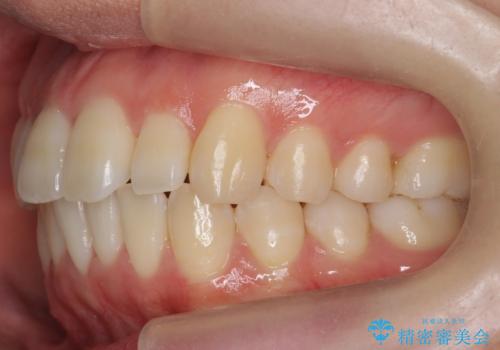

インビザライン モニター治療 前歯のねじれをまっすぐに

- 前歯のねじれを主訴に来院。

インビザラインの部分矯正コースではなく全体矯正コースをご希望でした。

前歯のねじれやがたつきだったため、モニター治療での低価格でのご提案が可能でした。

年齢が10代なこともあり、歯の動きは非常によく、リファインメントなしできれいに並びました。

下の前歯を少し削合して並べています。